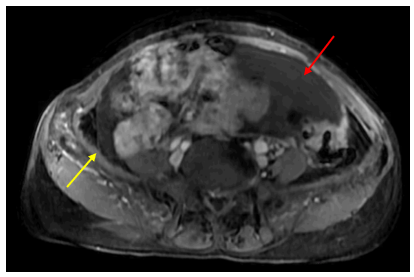

MRI tiểu khung:

Hình 5: Vị trí cạnh đáy tử cung hai bên có các đám ngấm thuốc mạnh, lớn nhất kích thước 18x19mm, ranh giới không rõ với lớp cơ ngoài tử cung và các quai ruột lân cận (mũi tên đỏ). Trực tràng xẹp, hạn chế đánh giá,sơ bộ thấy dày nhẹ thành trước trực tràng cao, dày nhất 7mm, trên đoạn dài 50mm, tăng ngấm thuốc nhẹ sau tiêm, không thấy mất cấu trúc lớp, không thấy thâm nhiễm ngoài thành (mũi tên vàng).

Hình 6: Nhiều dịch tự do ổ bụng, dày nhất do được ở tiểu khung ~35mm (mũi tên đỏ). Dày phúc mạc lan tỏa (mũi tên vàng).